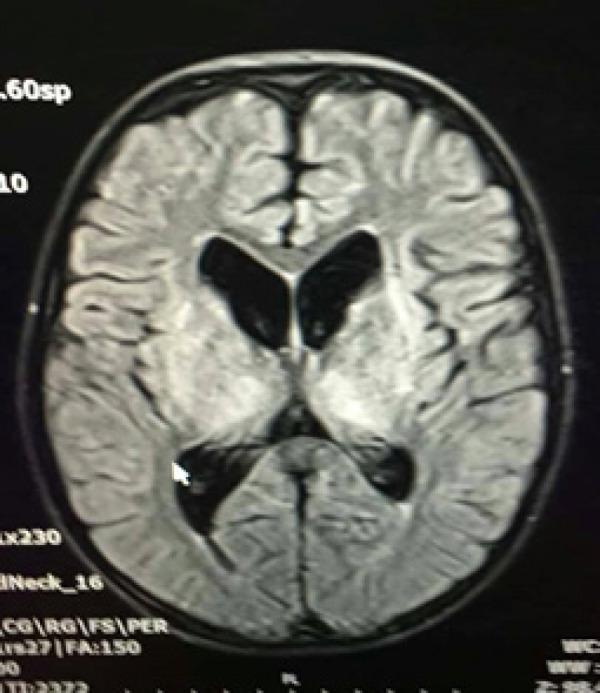

Wilson disease is an inherited disorder characterized by copper accumulation in various organs, leading to a wide range of clinical manifestations depending on the deposition site. Typically, symptoms of Wilson disease emerge between the ages of 5 and 35 years, primarily presenting with neurological and hepatic symptoms. This case report describes a 12-year-old boy diagnosed with Wilson disease based on low serum ceruloplasmin levels and elevated 24-hour urinary copper levels. His initial presentation included acute encephalopathy and tubulopathy with persistent hypokalemia. This case highlights the importance of a thorough evaluation, including neurological and renal assessments, to determine the underlying cause of acute encephalopathy, such as Wilson disease. Furthermore, this case shows that Wilson disease can manifest with neurological and kidney presentations despite a normal hepatic evaluation.

威尔逊病是一种遗传性疾病,其特征是铜在各个器官中蓄积,根据沉积部位的不同会导致广泛的临床表现。通常,威尔逊病的症状出现在5至35岁之间,主要表现为神经和肝脏症状。本病例报告描述了一名12岁男孩,根据血清铜蓝蛋白水平降低和24小时尿铜水平升高被诊断为威尔逊病。他最初的表现包括急性脑病和肾小管病伴持续性低钾血症。该病例强调了进行全面评估的重要性,包括神经和肾脏评估,以确定急性脑病的潜在病因,如威尔逊病。此外,该病例表明,尽管肝脏评估正常,但威尔逊病仍可表现为神经和肾脏症状。